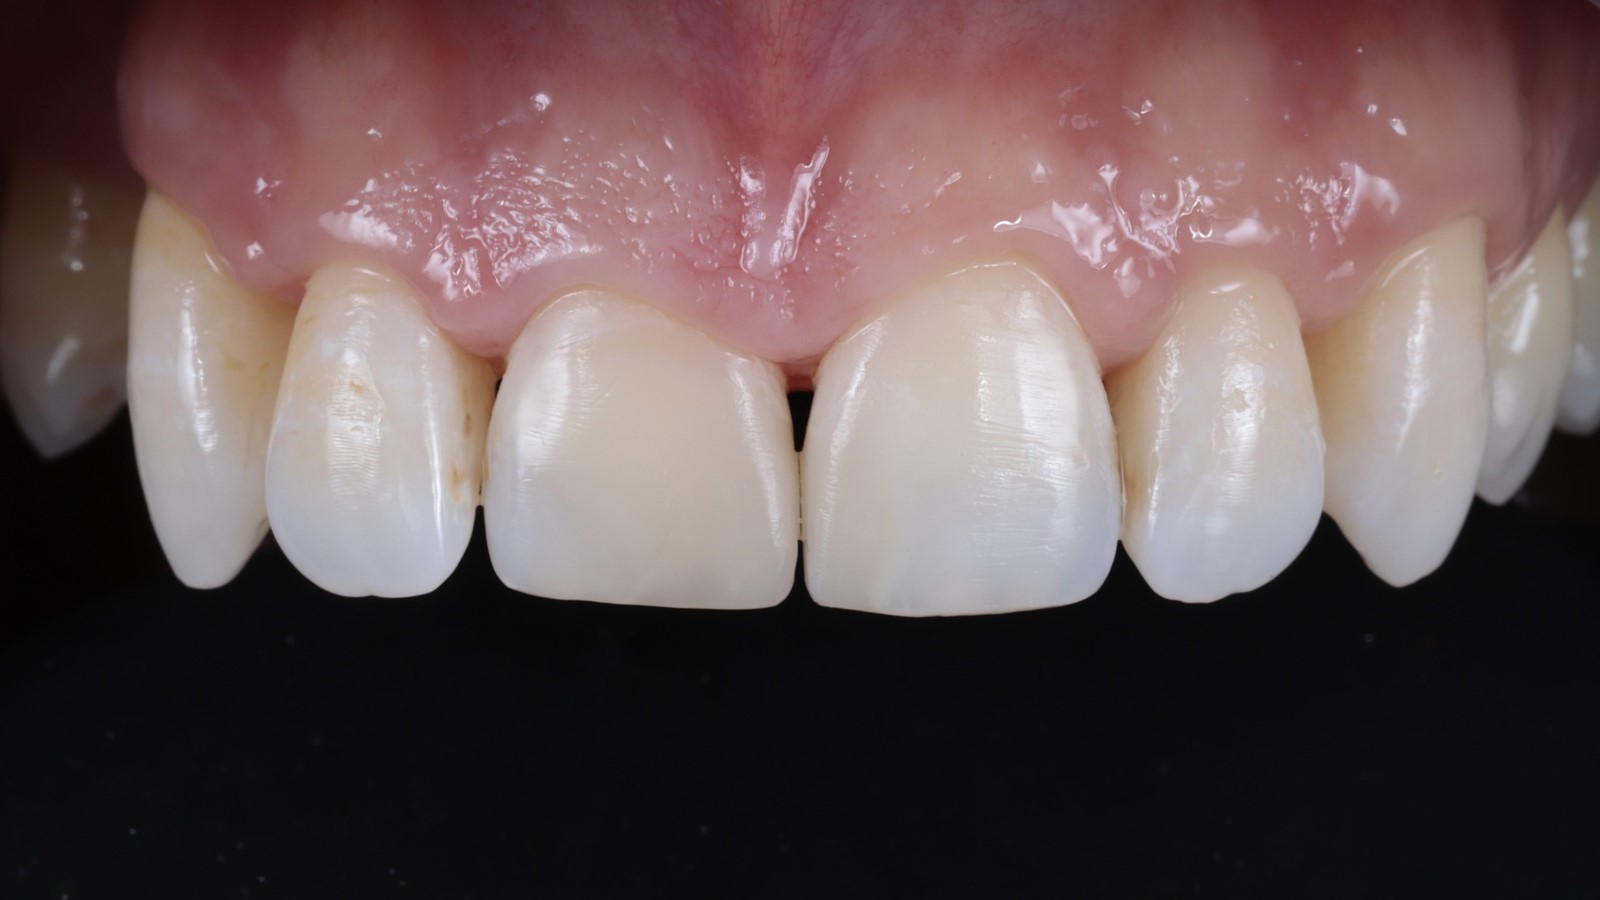

The dam was removed, and the finally polished restorations were revealed.

The restorations achieved complete integration with the natural tooth tissue after rehydration. The composite independently developed areas of translucency based on the thickness created, resulting in a highly aesthetic and natural appearance.